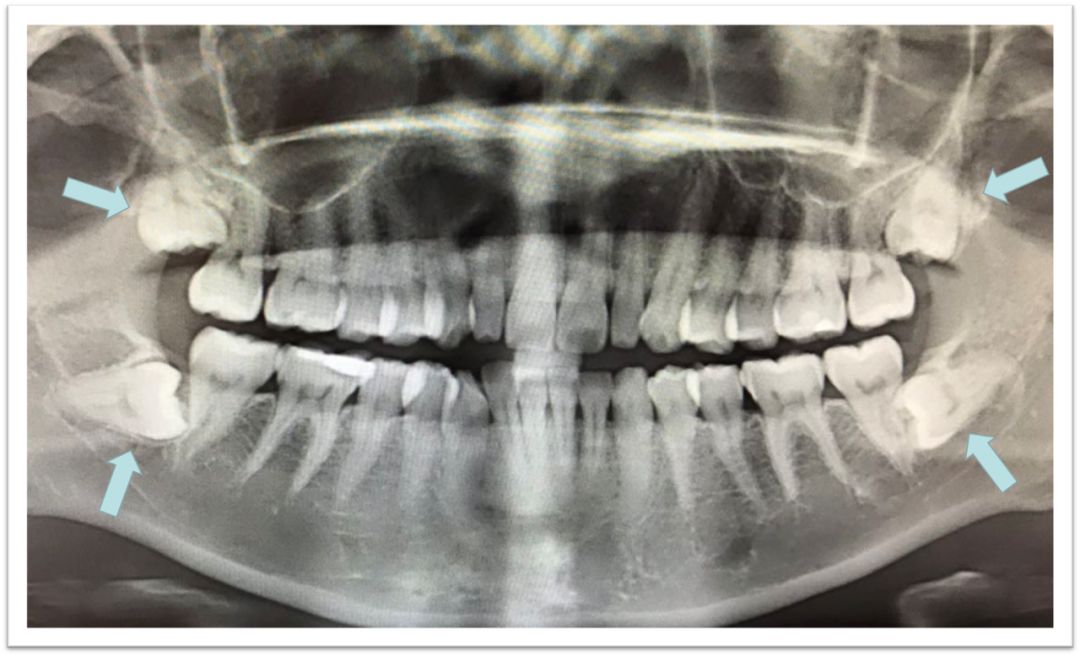

1、智齒阻生和发炎

这是大多数人前来拔除智齒的原因,因為生長嘅位置唔啱,导致智齒不能萌出到正常的咬合位置。阻生的智齒,通俗啲嚟講,就係“阻碍生长的智齒”,係指因為軟組織問題或者顎骨質量唔夠,智齒不能正常萌出,被牙齦或牙槽骨包圍住入面,經常引發炎症、疼痛。一般我们说牙疼拔智齒,很多就係阻生智齒,因為大部分甚至全部都埋伏喺顎骨入面,拔除嘅難度亦都相對較大,需要削掉一部分颌骨,再将智齒切碎取出。